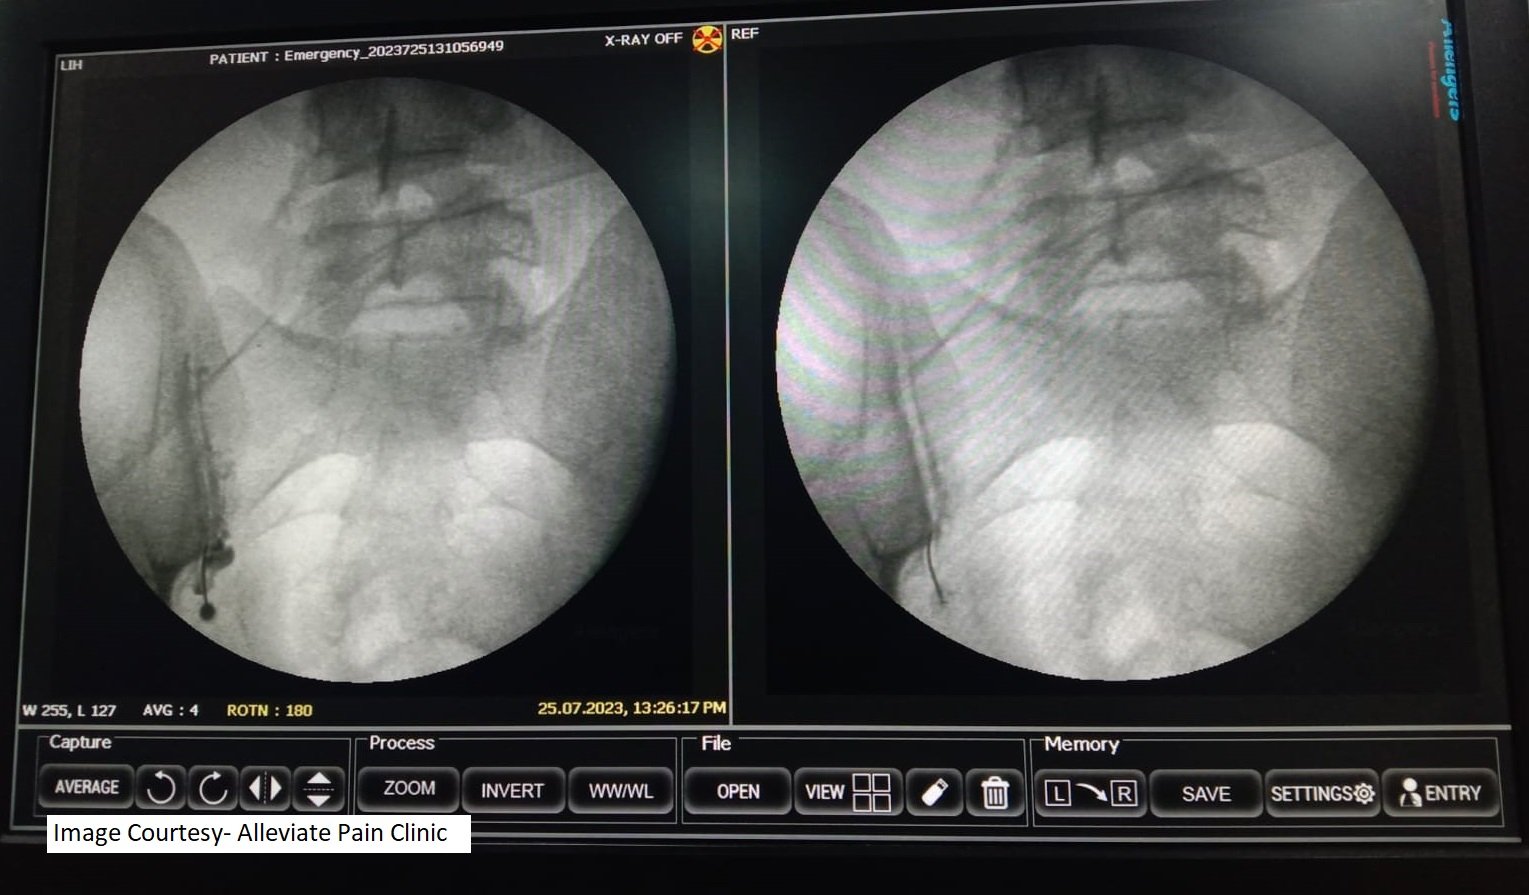

Fluoroscopy Guidance

Fluoroscopy is a real-time X-ray technique that allows the physician to visualize the SI joint and surrounding structures with precision. This helps guide the needle placement accurately.

A local anesthetic is administered to numb the skin and underlying tissue. Then, a thin, specialized needle is inserted into the SI joint, and contrast dye is injected to confirm the needle’s position. Once the correct placement is confirmed, a mixture of a corticosteroid and anesthetic is injected into the joint to reduce inflammation and alleviate pain.

Fluoroscopic guided Sacroiliac joint injection. Needle position confirmed by dye spread.However, the clinic’s approach didn’t stop at the injection. Prerna was also provided with a structured physiotherapy program to strengthen her core muscles and improve her overall spinal stability. This holistic approach addressed the root cause of her pain and provided her with the tools to maintain her improved quality of life.